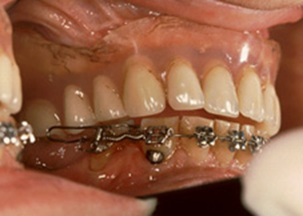

Fig 1 c-d (Bilder ortodontist Mats Larsson)